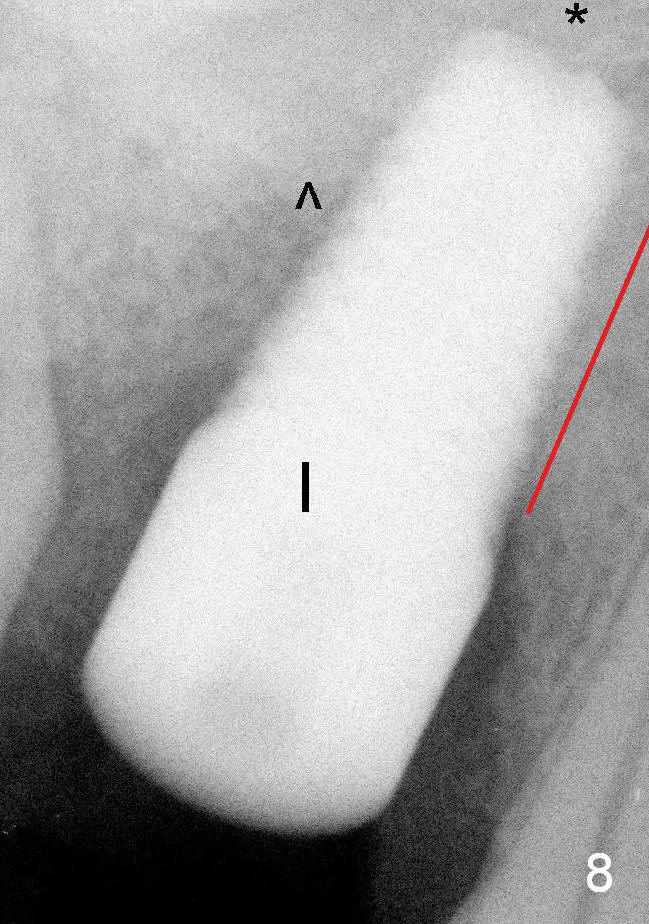

It appears that when a 7x17 mm implant is placed (Fig.8), the bone contact is increased vertically (red line) as the diameter of the implant increases. ^: sinus floor; *: bone present apical to the implant.